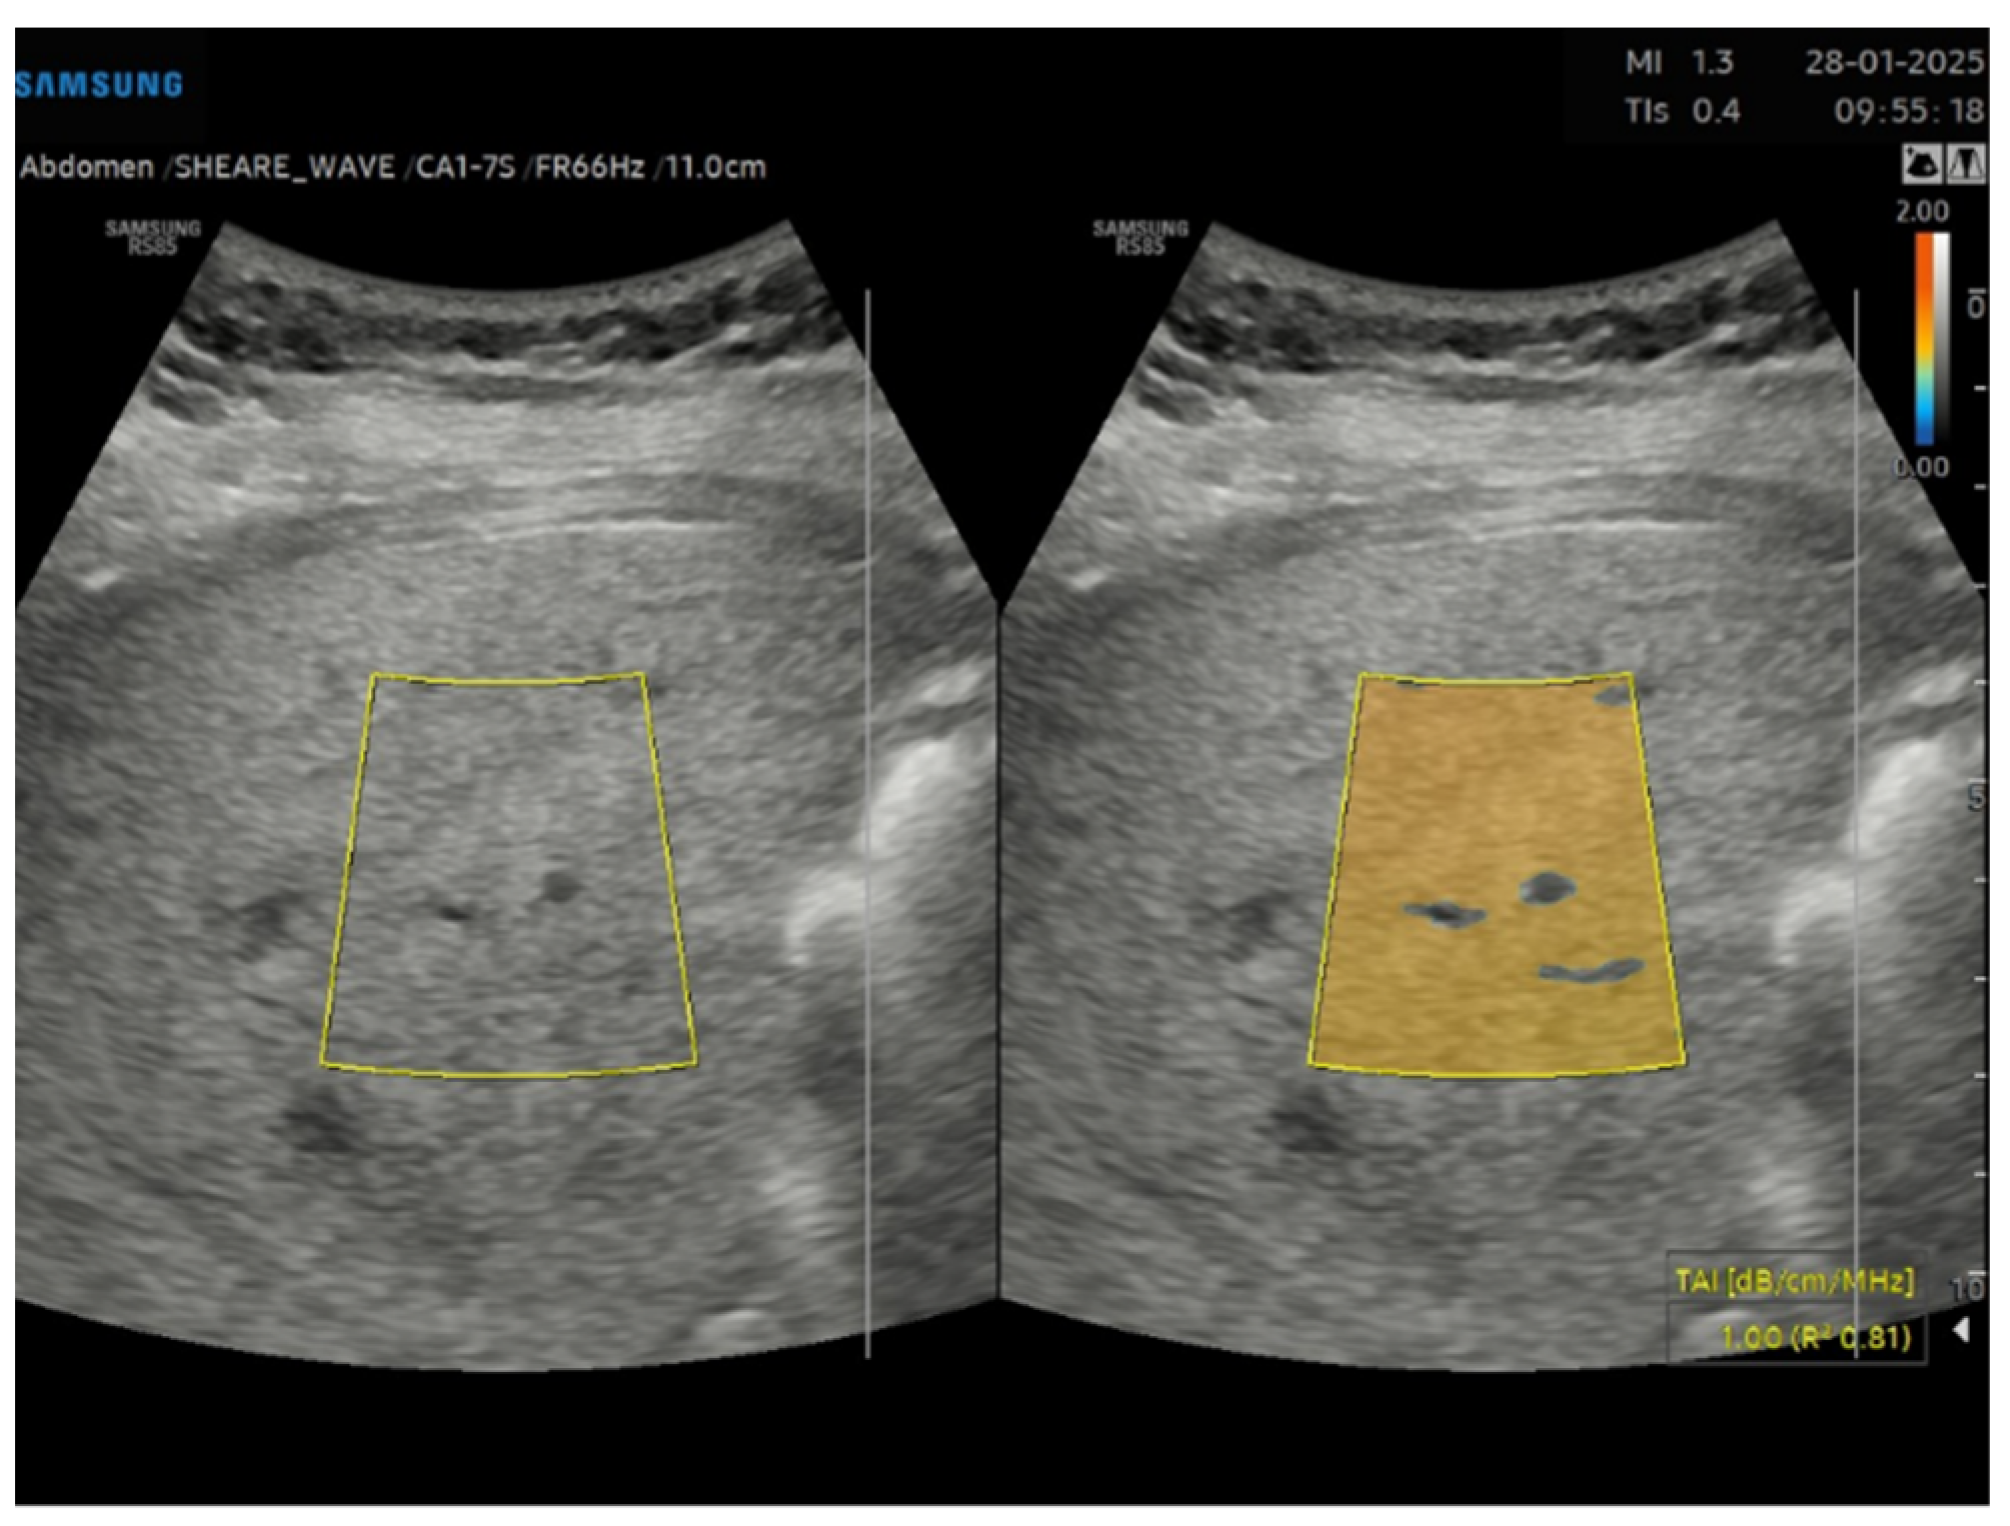

This is a cross-sectional observational study based on retrospectively collected ultrasound and clinical data. A total of 95 obese patients who underwent abdominal ultrasound examination as part of the preoperative assessment for potential bariatric surgery between November 2023 and April 2024 were evaluated. Ultrasound examinations were performed by expert echographers (with a minimum of 5 years’ experience in abdominal US) using Samsung RS85 Prestige system. The examination was performed after at least 6 h of fasting, with the patient in the supine position, using a right intercostal scanning approach. Each patient underwent conventional abdomen ultrasound with visual assessment of liver steatosis (Figure 1) and subsequently to the measurement of USFF with the Samsung CA1–7S (1 MHz–7 MHz) transducer. The ultrasonographic steatosis visual assessment and the USFF measurement were performed by different groups of operators in a blinded manner. TSI (Figure 2) and TAI (Figure 3) data were acquired and subsequently processed using proprietary algorithms developed and calibrated at the Samsung Medical Center [27,28]. These algorithms extracted relevant parameters, namely the attenuation coefficient and backscatter coefficient. A mathematical model grounded in established physical principles and incorporating empirical data, was then employed to translate these extracted parameters into an estimate of the liver USFF. Patients with clinical or morphological features of advanced liver diseases or cirrhosis, active viral hepatitis, alcohol use disorder, altered liver enzymes and heart failure were excluded. The collected data included age, gender, body mass index (BMI), TAI, TSI, USFF values, liver enzymes, comorbidities.

Figure 3. Tissue attenuation imaging (TAI) of a steatotic liver (S3) in a 33 years old male patient with grade III obesity.